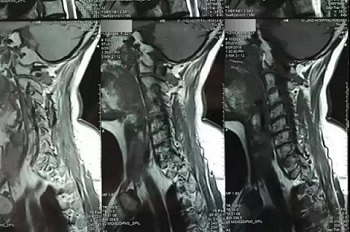

九、翻拍磁共振图像时,因为磁共振片子很大,而且一张片子上有很多图像(如下图),所以,单纯的拍一张片子,因为手机拍摄,像素以及翻拍质量不好,且放大后图像会发虚,细节看不清楚,所以,基本上是没用的,对于医生阅片来说,质量太差,不能获取图片上的有效信息。

十、因此需要将磁共振的一张片子,进行分区域局部放大拍摄,尽可能的将片子上的细节拍摄清楚,将一张磁共振片子进行分区。

十一、将分区的磁共振图像,按顺序进行拍摄,即可获取如下比较有价值的清晰图片